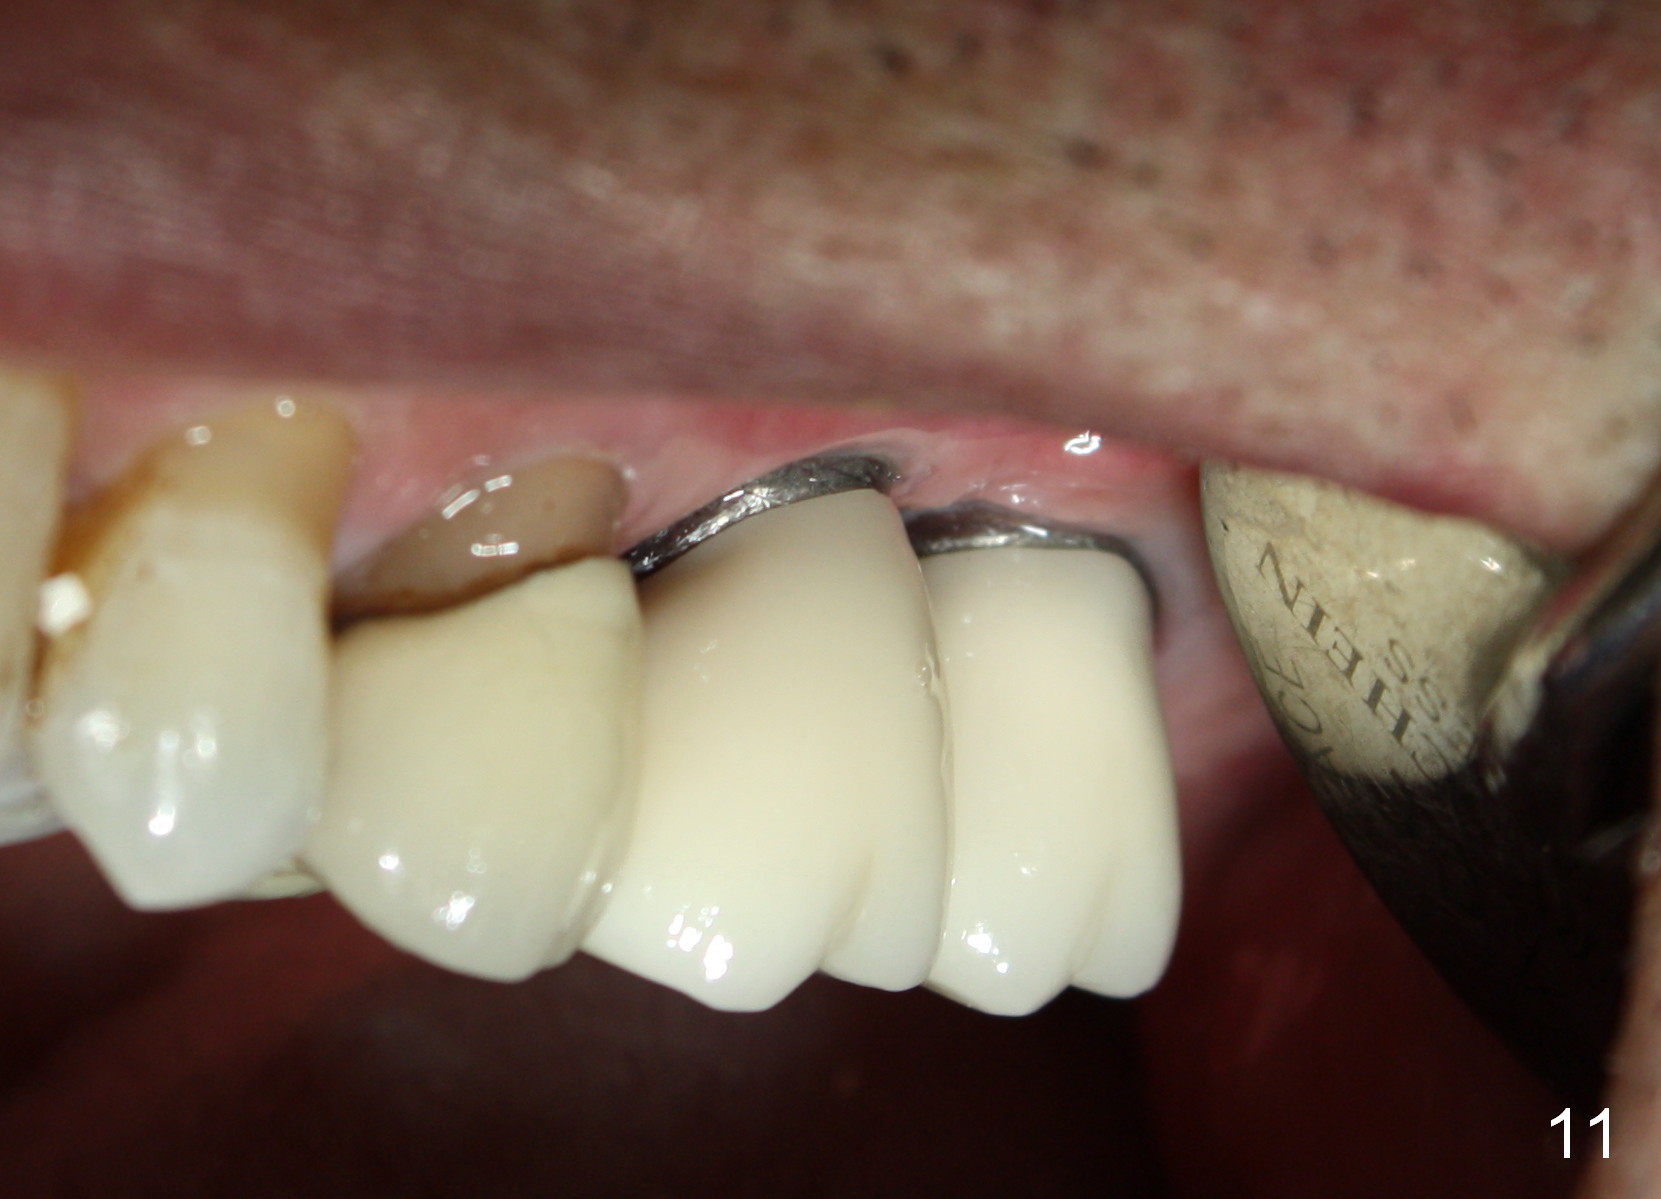

A 58-year-old man used to have a upper left 3-unit bridge. Two months after extraction and immediate implant at the site of the posterior abutment, an implant is planned to be placed at the site of the pontic, #14 (Fig.1). Osteotomy starts with a 1.6 mm pilot drill, followed by bone expanders, parallel to the crown of the tooth #13. The first intraop PA shows that 3.0 mm bone expander is close to the root of the neighboring tooth (Fig.2). No matter what is done to change the trajectory of the osteotomy using expanders according to the crown morphology of the neighboring tooth, the next 3 expander does not improve in parallelism (Fig.3). When a 6x17 mm tap is inserted (Fig.4 T), it is realized that axis of the tap is parallel to the axis of the crown of the neighboring tooth (black line), but not that of the root (red line). It is too late to change the trajectory drastically; a 6x17 mm implant is placed with insertion torque > 60 Ncm (Fig.5). It is best to change the trajectory as early as possible, e.g., after taking the first intraop PA and withdrawing the expander (Fig.6 black area) and as much as possible (red line; starting new osteotomy). It is quite similar to immediate implant. There is no bone loss 2 months postop (Fig.7), 18 months (Fig.8,9) or 34 months (Fig.10)post cementation, in spite of open contact between the crowns (Fig.10 black arrowhead). This is partially due to supragingival margin (Fig.11,12 (immediately pre-cementation)). No bone loss is noted 3 years 5 months post cementation (Fig.13).